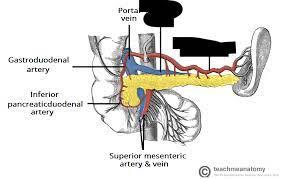

Celiac trunk

Common bile duct

Common hepatic artery

Duodenum

Hepatic portal vein

Left gastric artery/vein

Liver

Pancreas

Pancreatic duct

Splenic artery/vein

Superior/inferior mesenteric artery